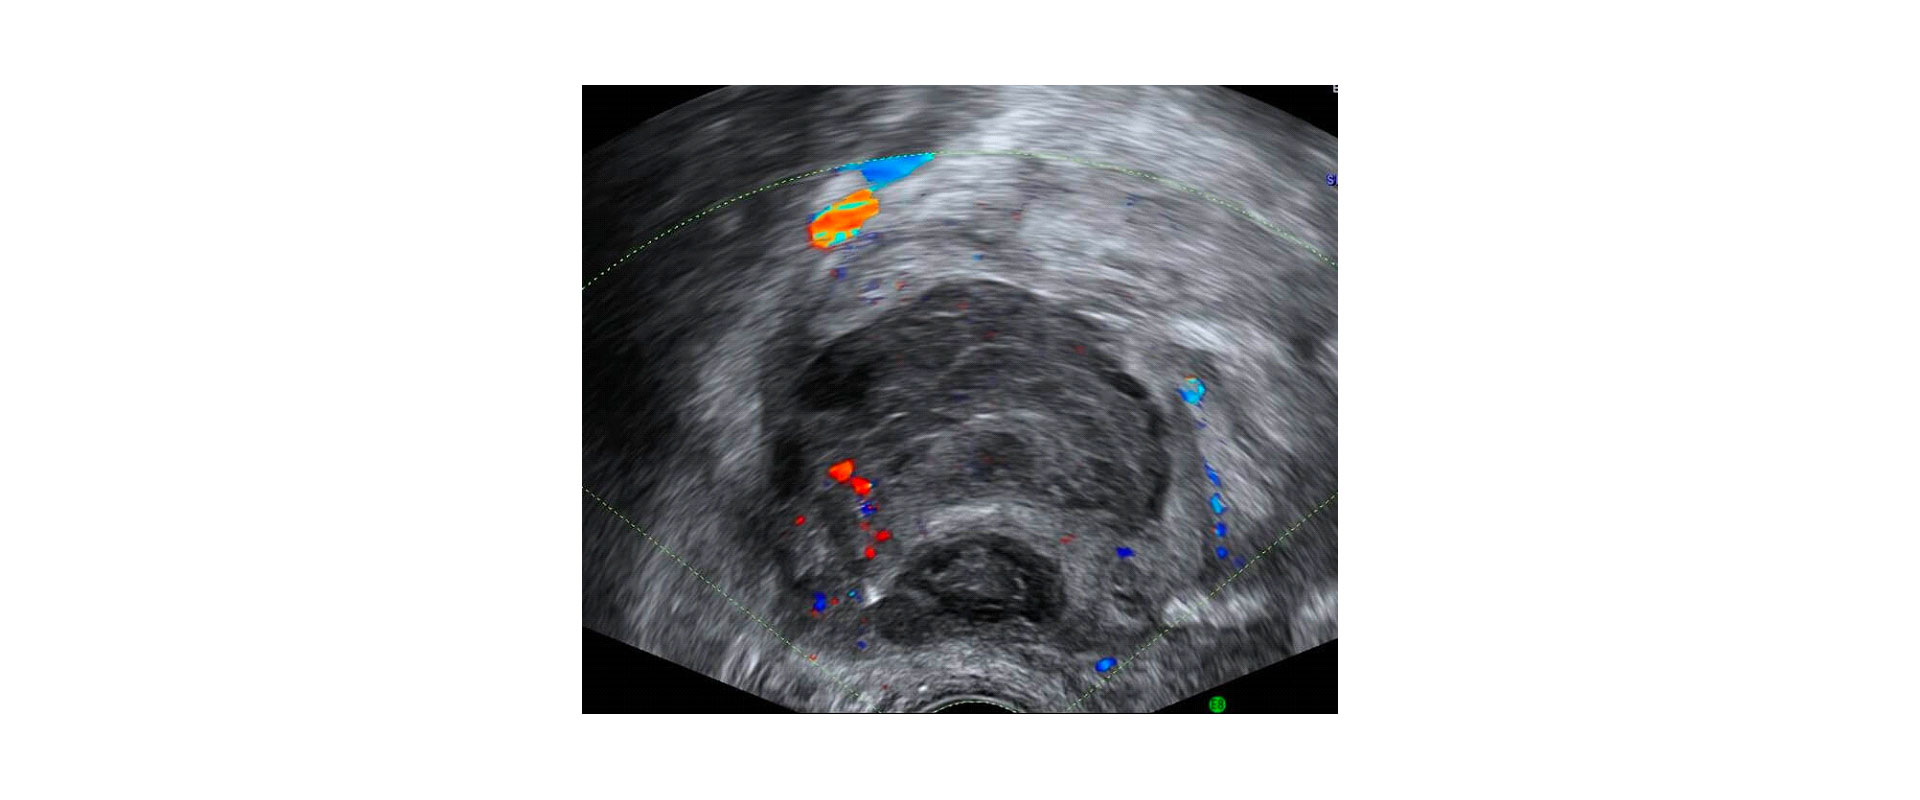

⦁ Διακολπικό υπερηχογράφημα